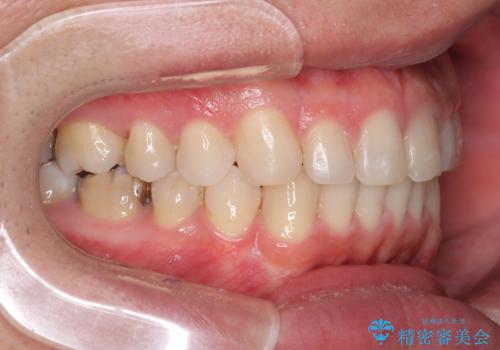

正中離開・クロスバイト・すきっ歯・叢生|インビザラインで治療

- 前歯の隙間と歯のデコボコを主訴にご来院された患者様です。

加えて、上下の奥歯が全く咬み合わないシザーズバイトの状態も認められました。

矯正検査の結果、非抜歯でインビザラインによる治療が可能と判断し、治療を行いました。

歯の隙間とデコボコ、シザーズバイトも改善され、咬み合わせや見た目が整い、患者様にも大変ご満足いただけました。